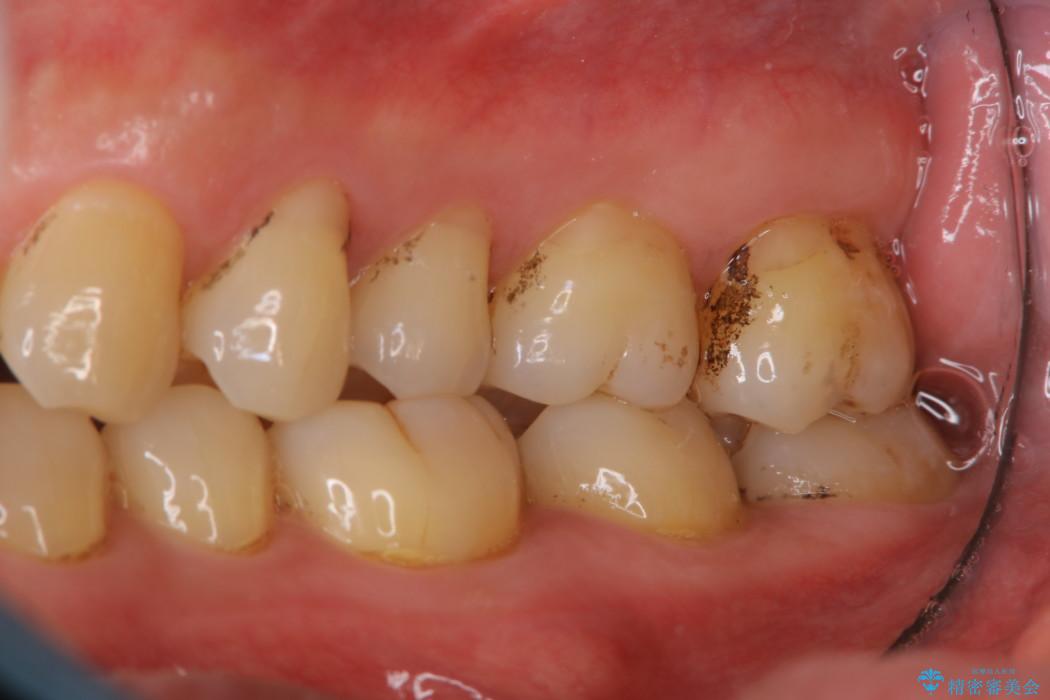

【40代男性】歯にこびりついた着色のクリーニング

普段からコーヒーをよく飲まれる方で、3年間歯医者に行かれておらず、定期健診も込みでご来院されました。

堅くこびりついていたステインも1時間コースのPMTC(プロフェッショナルクリーニング)できれいな状態になりました。